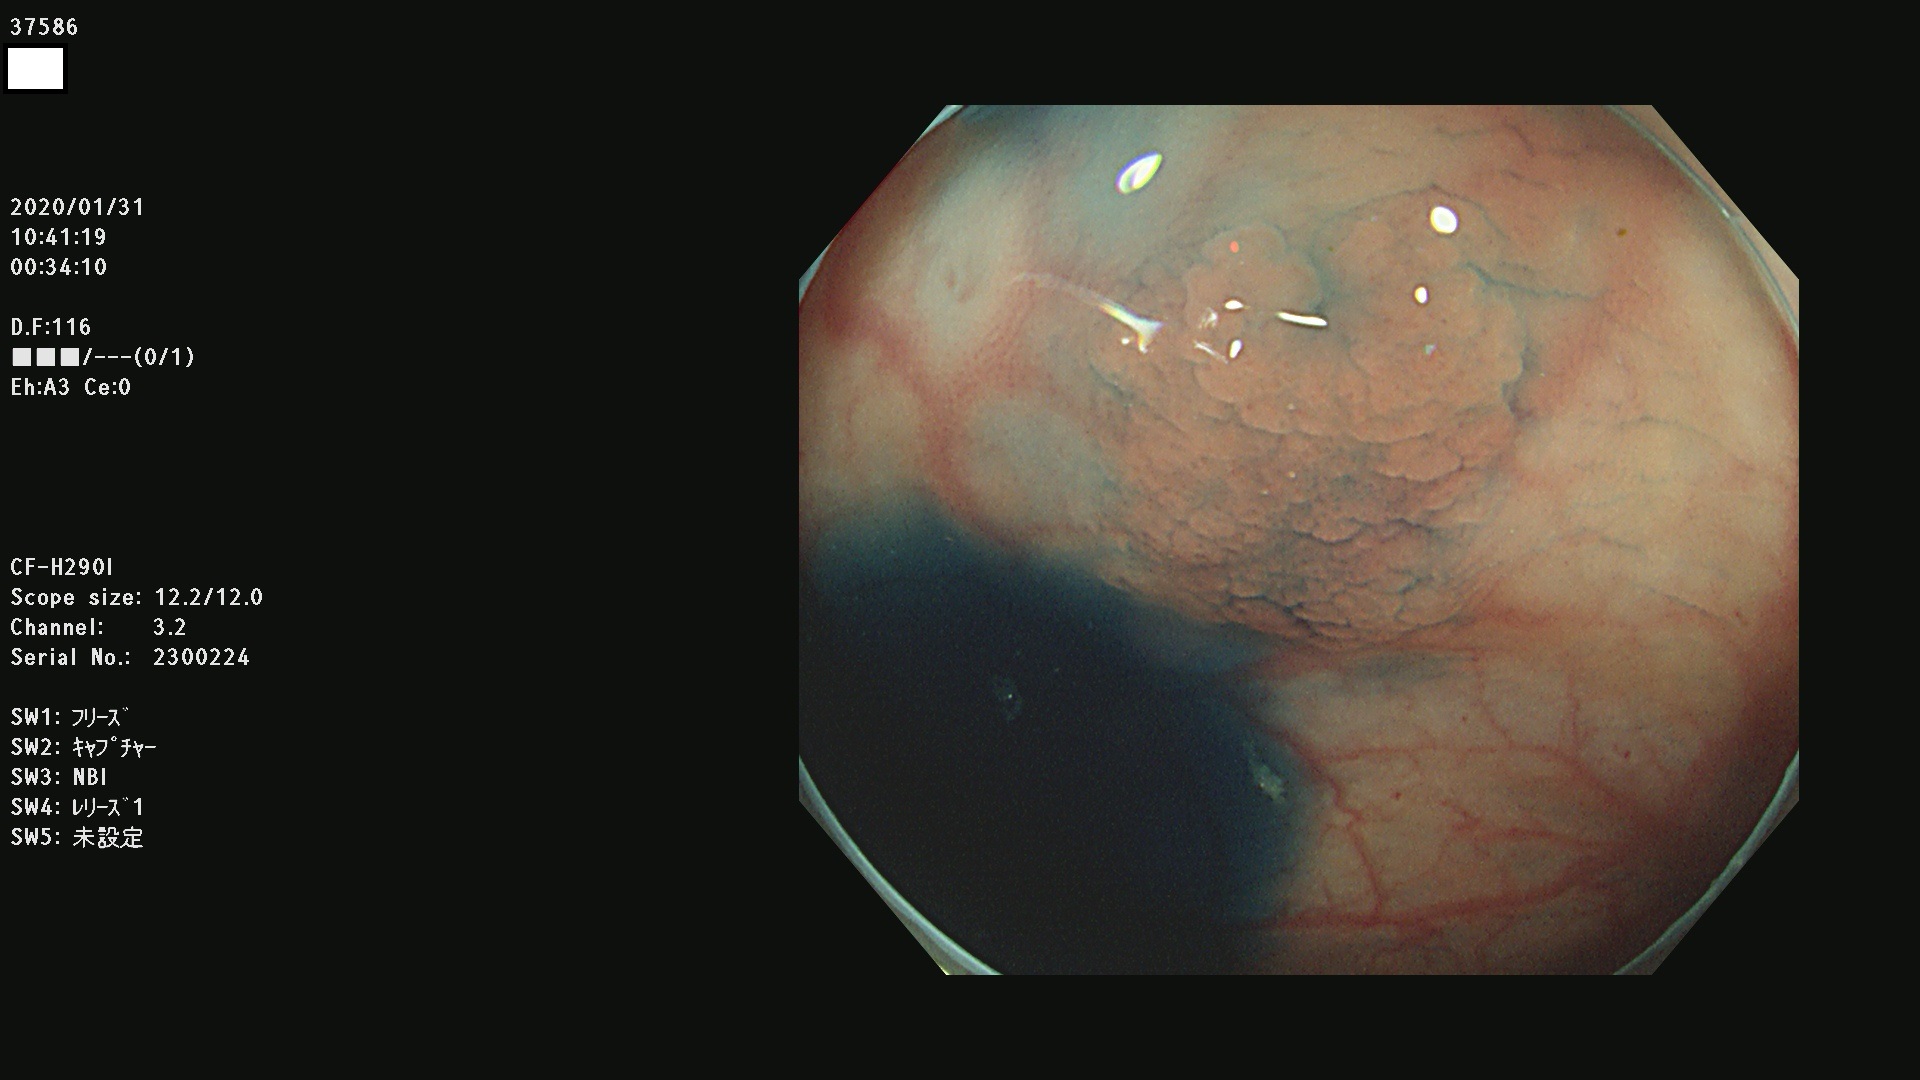

発見困難で危険性の高い平坦型病変(上記100名より抽出) ![]()